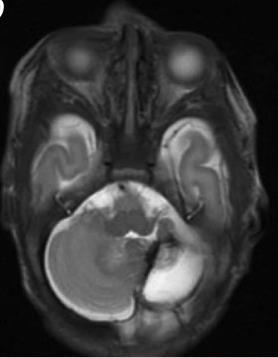

Germinal matrix-intraventricular haemorrhage (GMH-IVH)

Focal infarction

White matter injury

Global injury from hypoxic-ischaemic encephalopathy (HIE)